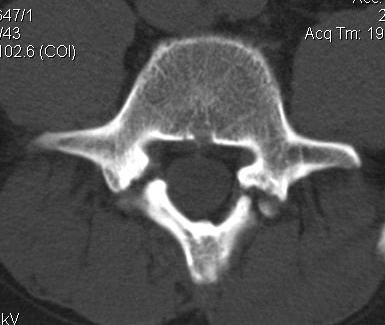

The disc simply provides cushion between the vertebrae. At least half of all disc herniations do not require surgery. Surgery is required when the disc has degenerated enough to allow displacement of one vertebra vs another, thereby causing nerve impingement, or if extruded disc material causes nerve impingement. The impingement may lead to deterioration of the nerve and the subsequent musculature, and therefore needs to be addressed.